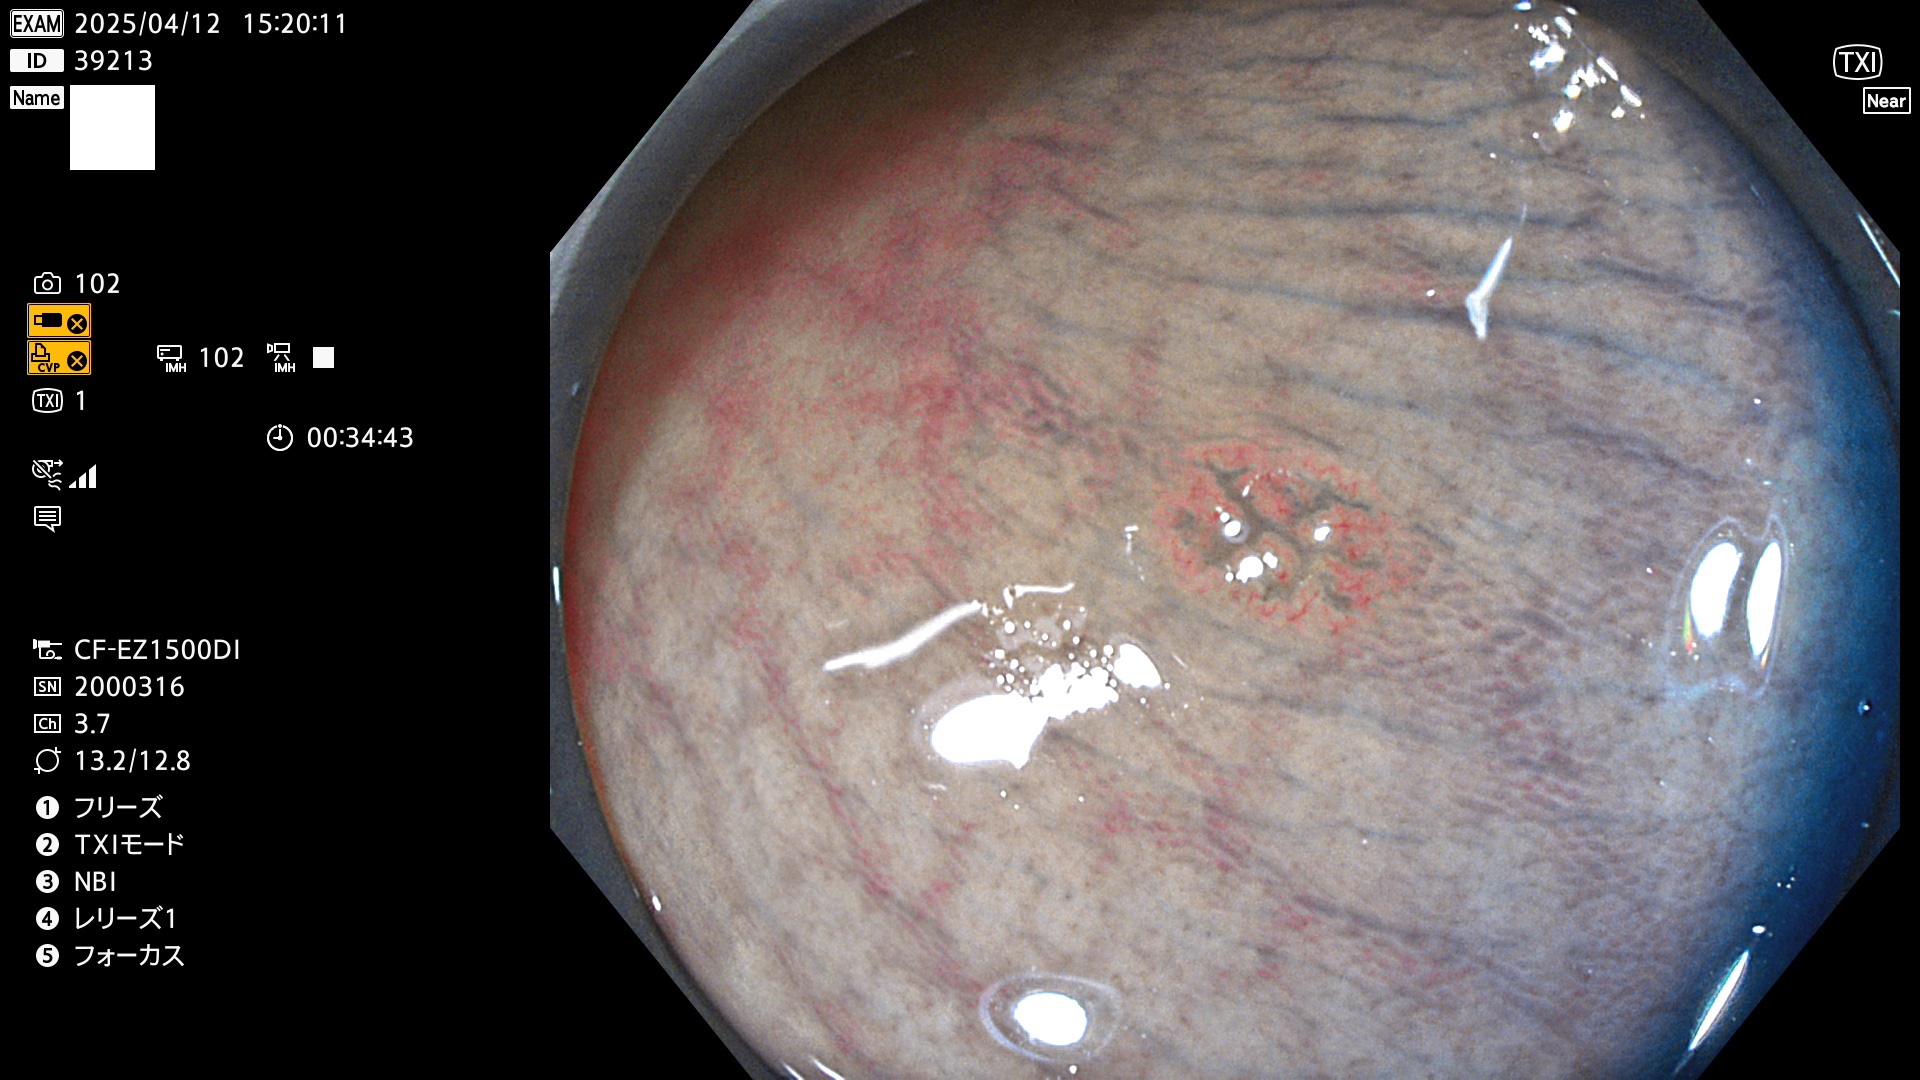

完全に平坦な物をUb、陥凹している物をUcと呼びます。Ubは認識が困難で、Ucはびらん(炎症)と紛らわしいために見落とされやすく、「内視鏡後・大腸癌」の原因になります。

抽出の対象期間 2025年4月10日〜4月13日の4日間(48件の検査)11個 (4/48=23%)

びらんと鑑別の困難なUc型腺腫